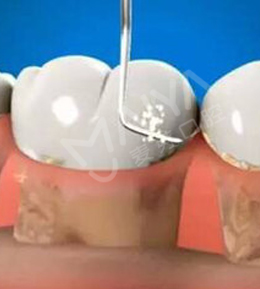

针对牙周炎、不良修复体导致的牙周袋, 麦芽龈下刮治术通过精密器械,清除根面结石和菌斑创口小愈合快,但建议根治牙周炎或更换不良修复体,才能治本

适应症:牙龈炎、牙周炎、 牙周袋、不良修复体引起的口臭